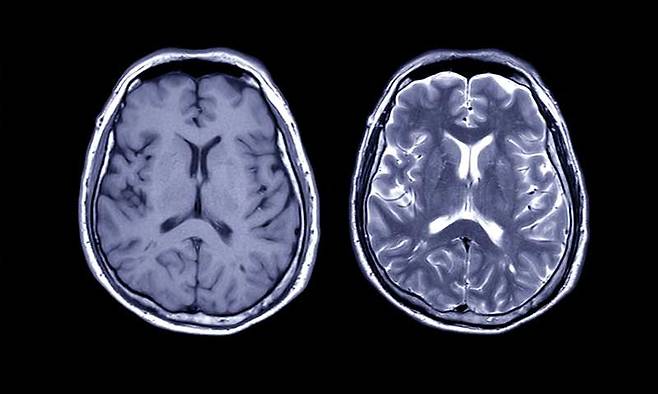

너무 짧으면 체온과 혈류 변화가 충분히 올라오지 않고 너무 길면 피로와 각성이 과해져 책상 앞에 앉았을 때 집중이 흐트러진다. 30분은 속도와 호흡을 올리되 과도한 피로를 남기지 않는 현실적인 균형점이다. 자각 난이도 기준으로 숨이 차서 긴 문장을 말하기는 어렵지만 짧은 대화는 가능한 정도가 적당하다. 이 강도에서 해마의 가소성을 돕는 신경영양 인자가 증가하고 전두엽의 잡음이 줄어 목표 지향적 주의가 붙는다. 쉽게 말해 연필을 잡자마자 집중이 되는 환경을 몸이 먼저 마련해 준다.

학습 전에 걷기는 입력을 선명하게 만든다. 암기나 이해가 필요한 공부를 앞두고 1시간에서 2시간 전에 30분 걷기를 배치하면 새로운 정보를 붙잡는 능력이 올라간다. 학습 직후의 걷기는 저장을 단단하게 만든다. 문제를 풀고 난 뒤 10분 정도 가벼운 산책을 더하면 방금 배운 내용이 장기 기억으로 넘어가는 효율이 좋아진다. 밤에는 과도한 각성을 피하기 위해 속도를 낮추고 길이를 줄인다. 늦은 시간 오래 걸으면 잠이 늦어질 수 있으므로 취침 세 시간 전 이후에는 가벼운 정리 걷기로 마무리한다.

걷기 30분은 체력을 위한 시간이 아니라 학습을 위한 투자다. 적당한 심박과 호흡, 규칙적인 리듬이 해마의 문을 열고 전두엽의 잡음을 줄인다. 중요한 것은 가끔의 장거리보다 매일의 짧은 일관성이다. 오늘 30분이 내일의 집중 시간을 당겨 오고, 오늘의 10분 산책이 어젯밤의 공부를 오래 붙들어 준다. 걷기는 의지가 아니라 구조의 문제다. 코스를 정하고 시각을 고정하면 뇌는 그 시간에 집중할 준비를 먼저 한다. 머리가 둔한 날일수록 신발 끈을 먼저 묶는 이유가 여기에 있다.